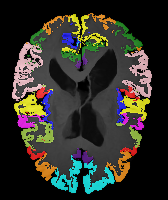

Image Manual Seg DA-1 Mono-21 DA-21 Mono-65 Refer to caption Refer to caption Refer to caption Refer to caption Refer to caption Refer to caption

Figure 2:  Examples of knee MRI registration (top) and brain MRI segmentation (bottom) results. Top: The first two columns are the moving image/segmentation and the target image/segmentation followed by the warped moving images (with deformation grids)/segmentations by different models. Bottom left to right: original image, manual segmentation, and predictions of various models. Mono-i𝑖i and DA-i𝑖i represent the mono- and DA models with i𝑖i manual segmentations respectively.

Results: All trained networks are evaluated using Dice overlap scores between predictions and the manual segmentations for the segmentation network, or between the warped moving segmentations and the target segmentations for the registration network. Tabs. 1 and 2 show results for the knee and brain MRI experiments respectively in Dice scores (%). Fig. 2 shows examples of knee MRI registrations and brain MRI segmentations.

Brain results: Dice scores for segmentation and registration increase by about 2.6 and 3.5 respectively for the cortical structures of the brain MRIs.

Qualitative results: DA achieves more anatomically consistent registrations than the mono-networks on the knee (Fig. 2) and Brain MRI samples (see supplementary material).